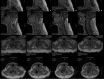

Figure 2. MRI cervical with and without contrast further characterizing mass

(A) Left parasagittal cervical MRI with contrast demonstrating heterogeneously enhancing mass (red arrows) originating from the facets with extension into the soft tissues of the neck. (B) Sagittal MRI with contrast demonstrating extradural mass of the posterior elements with extension into the soft tissues. (C) Axial MRI with contrast at the level of C6 shows mass involvement with the left facet and abuttal of the left vertebral artery. (D) Axial MRI with contrast at the level of C7 showing mass involvement of the left facet and abuttal with possible encasement of the left vertebral artery (yellow arrow) MRI: magnetic resonance imaging